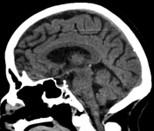

History of Ischemic Stroke

2 years ago. Diagnosed as a left middle cerebral artery (MCA) lacunar infarct.

• Sequelae: Mild, persistent weakness in his left leg. He walks with a slight limp but is fully independent and ambulatory, with no residual arm or speech deficits.

• Previous CT-scan: